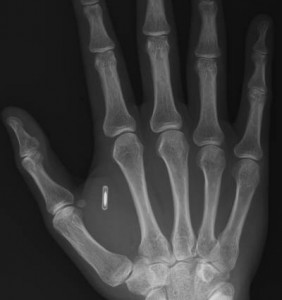

- Healthcare: There are hundreds of applications robotics in healthcare and medicine. Robotic surgeons, like the da Vinci robot, will perform more accurate surgeries without the limitations of humans (shaky hands, lack of sensors, viewpoint limitations). Robot nurses will patrol the hallways of hospitals monitoring the vitals of patients and alerting doctors to urgent situations. Telepresence robots will allow the best diagnostician to beam in and consult on your case. Robots will help nurses lift heavy patients, and other robots will provide affection and mental stimulation to the old and frail.